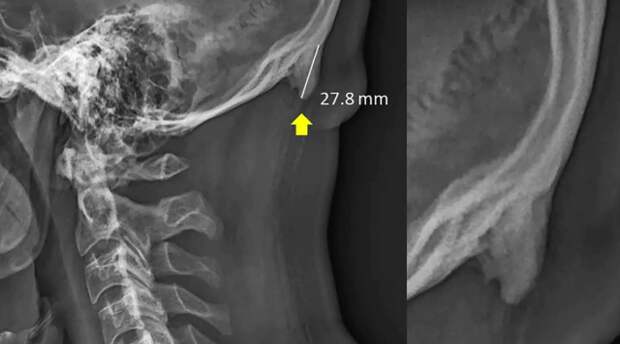

В результате у людей прямо над шеей появляется небольшая выпуклость или рог.

Ученые отмечают, что на изменения осанки и рост рогов у людей влияют современные технологии. Мобильные устройства искажают человеческие позвонки, пользователи вынуждены наклонять голову вперед, чтобы посмотреть на экран телефона.